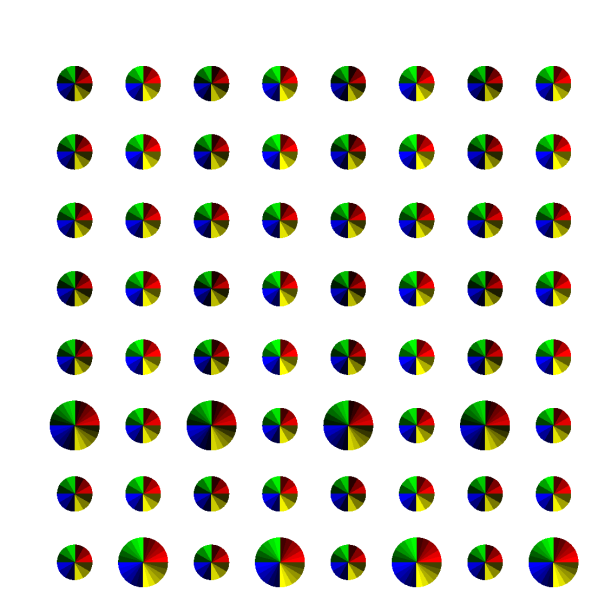

Figure 1 shows a 8×8888\times 8 patch of k-space generated by the patterns with acceleration factor 𝑹=[2,3]𝑹23\bm{R}=[2,3] and Q=72𝑄72Q=72. In this visualisation, each pie slice corresponds to one readout and has a constant area. Hence, the area of each pie corresponds to the number of times with which that k-space position is sampled in the entire acquisition.

Refer to caption

(a) Regular

(b) Treg

(c) Sreg

(d) TSreg

(e) Random

(f) Halton

(g) Legend

Fig. 1: Graphical representation of undersampling patterns for 𝑹=[2,3]𝑹23\bm{R}=[2,3], k-space size of 8×8888\times 8 and number of contrasts Q=72𝑄72Q=72. Legend: each row represents a set of contrasts, grouped together with according to contrast property such as inversion times.